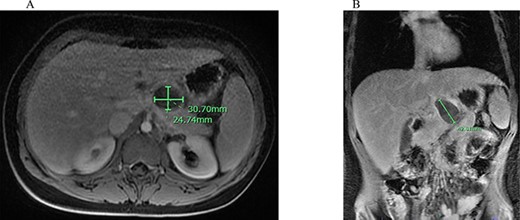

An abdominal ultrasound (US) demonstrated a peripancreatic cystic mass with internal debris located between the stomach and pancreas (Fig. 1). The differential diagnosis at that time included a foregut duplication cyst, an infradiaphragmatic sequestration and a pancreatic cystic lesion. Given the unclear origin of this lesion, an abdominal magnetic resonance imaging (MRI) was obtained, which identified a T1 hypointense and T2 hyperintense rim enhancing 4.3-cm mass with surrounding edema and adjacent peripancreatic inflammation (Fig. 2).

Abdominal MRI of suspicious mass; (A) axial abdominal MRI revealing 3.07 × 2.74 cm mass (green bars) posterior to the L. lobe of the liver and medial to the stomach; (B) coronal abdominal MRI demonstrating 4.26 cm mass (green bar) inferior to the liver and superior to the pancreas with peripancreatic inflammation.